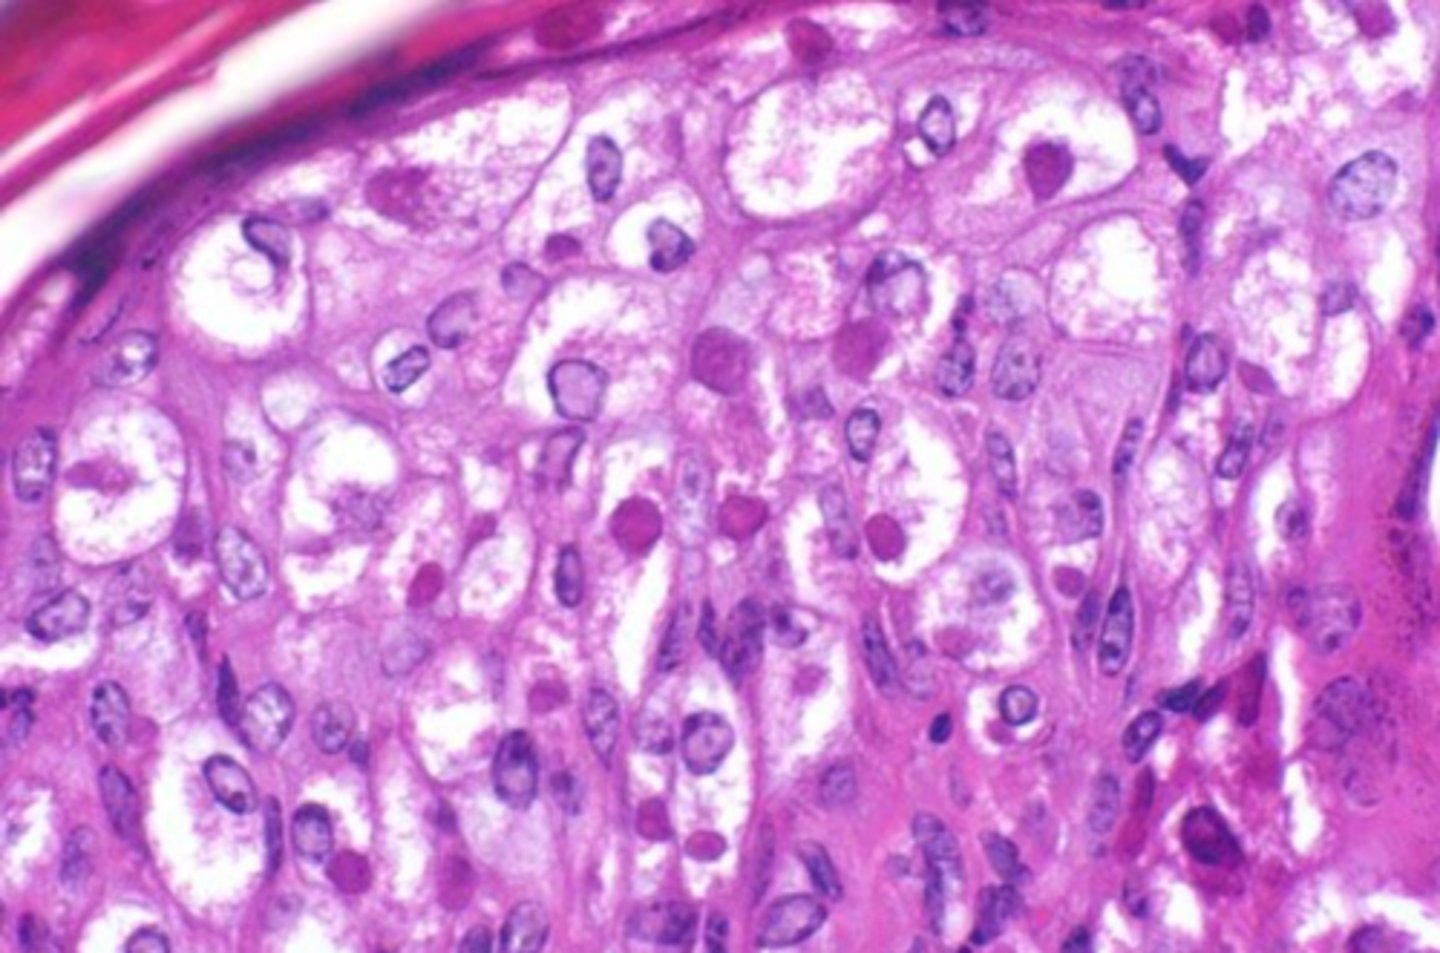

hepatocellular vacuolar change - glycogen type (glycogen in cytoplasm)

Both of these images are showing what?

<p>Both of these images are showing what?</p>

clear granules/vacuoles, "feathered cytoplasm", not displaced nuclei

what are the microscopic features of glycogen in the cytoplasm?